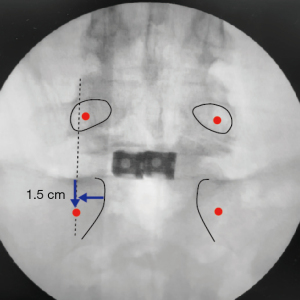

Initially, TLIF at L5-S1 was conducted using two cages, accessed either through a 4-cm longitudinal median incision or the Wiltse approach via a paramedian incision. Under fluoroscopic guidance, it is crucial to align the tilt of the S1 endplate with the fluoroscopic angle in the anteroposterior view. The entry point for S1 was located 1.5 cm caudal to the edge of the S1 upper endplate and 1.5 cm lateral to the medial border of the S1 pedicle, which is typically located in the lateral wall of L5 (Figure 2). The PSEPS trajectory was angled 20° inward toward the anterior third of the S1 endplate. A conventional straight probe was inserted and directed cephalad until it reached the cranial margin of the S1 end plate (Figure 3A,3B). The placement of the probe beyond the posterior wall of the vertebral body was confirmed in the lateral view (Figure 3C). The M-probe was replaced with a guidewire, and the guidewire was replaced with a cannula before advancing the M-probe toward the anterior third of the S1 vertebral endplate using a hummer. The cephalocaudal orientation of the trajectory was adjusted by rotating the tip of the M-probe by 180° (Figure 4A-4C). When the tip arrived at the S1 endplate, the M-probe was oriented cephalad and advanced forward to penetrate the endplate (Figure 4D-4F). Rotating the tip of the M-probe enlarges the bone hole in the S1 endplate and eliminates the need for tapping. Finally, a guidewire was used to verify the position of the tip in the intervertebral disc, followed by the insertion of the S1 PSs. The L5 PSs was placed using a conventional straight probe. Intraoperative C-arm images demonstrated the optimal positioning of the S1 screw (Figure 5). Precept spinal system screws (NUVASIVE) was used for all patients.